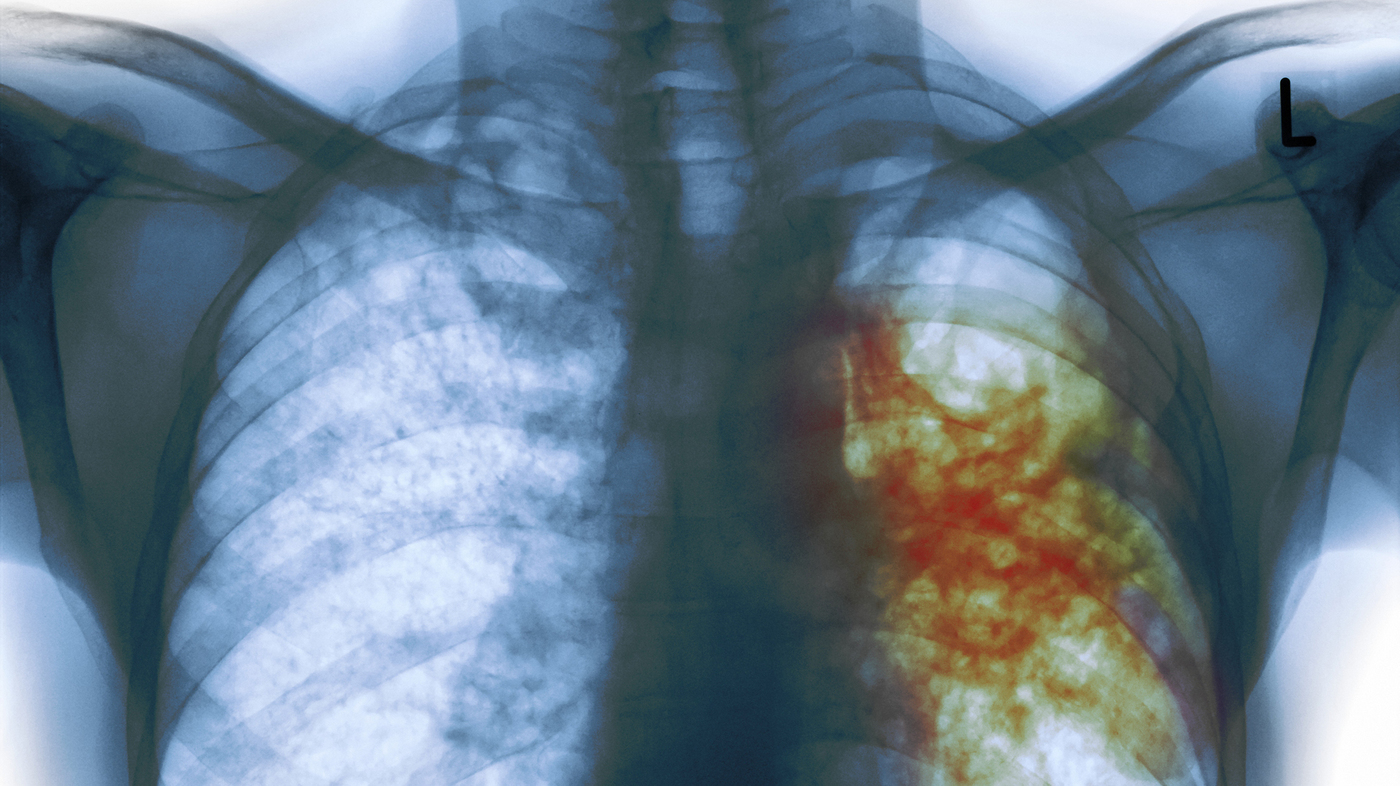

New tuberculosis (TB) ethics guidance, launched today by the World Health Organization (WHO), aims to help ensure that countries implementing the End TB Strategy adhere to sound ethical standards to protect the rights of all those affected. TB, the world’s top infectious disease killer, claims 5 000 lives each day. The heaviest burden is carried